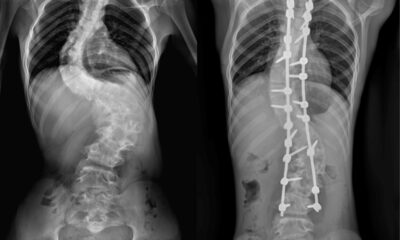

Сколиоз, кифоз, лордоз — искривления позвоночника;

Современные методы диагностики (МРТ, КТ, рентген) и лечения (ЛФК, мануальная терапия, медикаменты) позволяют успешно справляться с большинством заболеваний позвоночника без операции.

Команды ННИИТО им. Цивьяна и НМИЦ им. Мешалкина провели совместное вмешательство для спасения девушки со сломанной системой...

Врачи отделения травматологии и ортопедии РДКБ РНИМУ им. Н.И. Пирогова Минздрава России провели успешную операцию по коррекции...